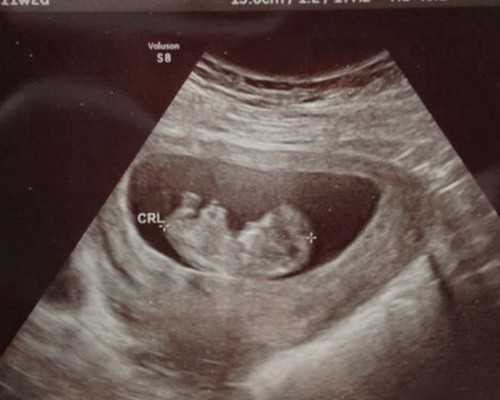

判断是否怀孕的前提是有正常性生活,且没有避孕,然后有出现停经史就要怀疑可能是怀孕了。也要结合自身月经周期进行判断,如果月经推迟一周以上就可以做早孕检测是否怀孕了。可以用早孕试纸测早晨起来的晨尿,如果双杠则为阳性,提示有怀孕。再通过医院的血HCG检查可确诊。或者月经推迟10天以上,可做超声检查判断胚胎发育情况及是否宫内孕。若月经平时不规律,可在同房后10天左右通过晨尿使用早孕试纸进行测孕。有些女性会在停经后出现早孕反应,比如头晕、恶心、呕吐、嗜睡等考虑是怀孕,具体以检查为准。